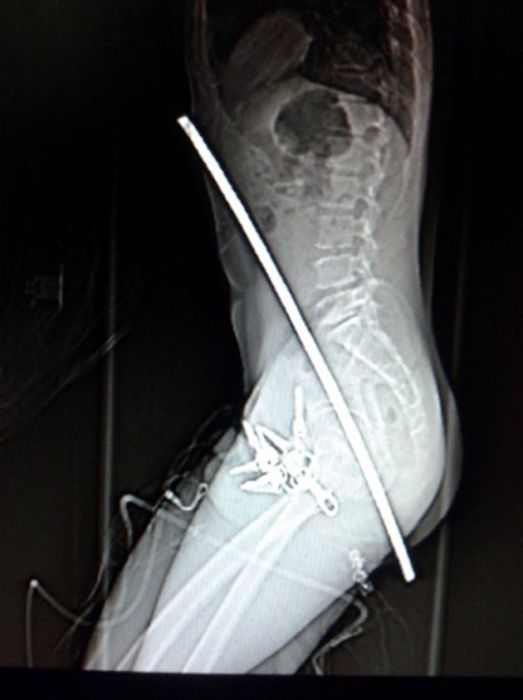

Рентгеновские снимки людей, которые умудрились сами или с чужой помощью разместить внутри своего организма разные посторонние предметы. От вилок и ножей до пуль и бензопилы (!!!). По этическим соображениям обычные снимки таких травм и повреждений выкладывать нельзя, зато рентгеновские можно – на них травмы видны достаточно условно, хоть и очень понятно.